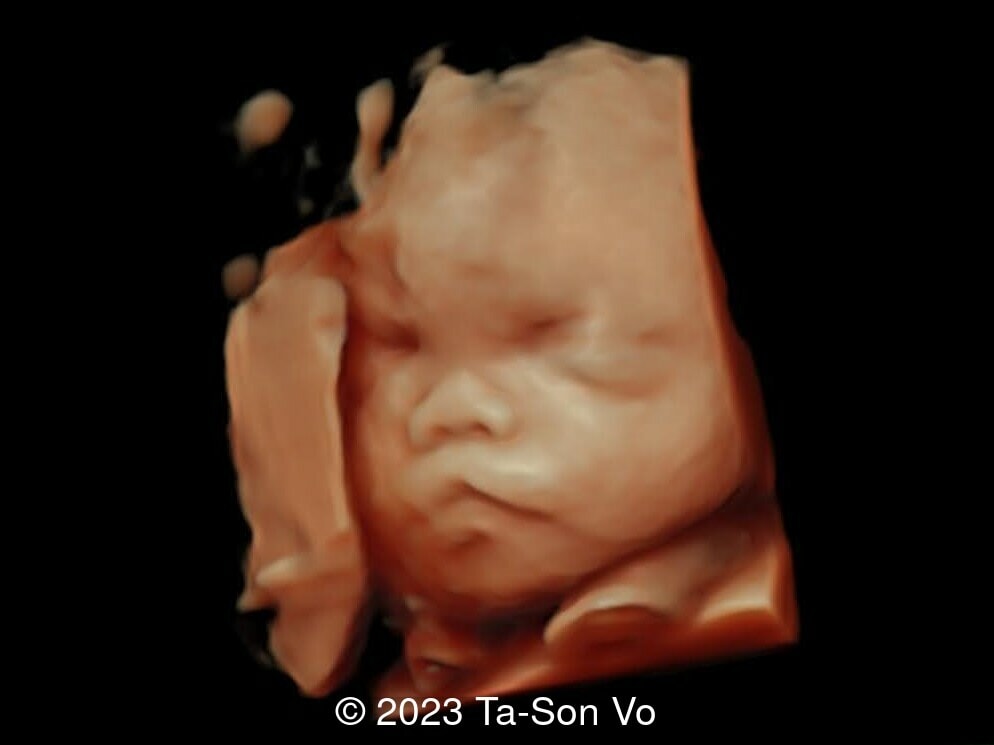

Level 2 ultrasound at 23 weeks and 28 weeks of gestation revealed thick nuchal and prenasal skin (Image 1), frontal bossing (Image 1,2), facial dysmorphism with a short nose, anteverted nostrils, flat nasal bridge, and long philtrum (Image 3,4), hypertelorism (Image 5), mega cisterna magna (Image 6) and polyhydramnios (Image 7). There was neither congenital diaphragmatic hernia nor cardiac defects with only mild tricuspid regurgitation (Image 8). Fetal biometry demonstrates a large head with rhizomelic limb shortening (Image 9).